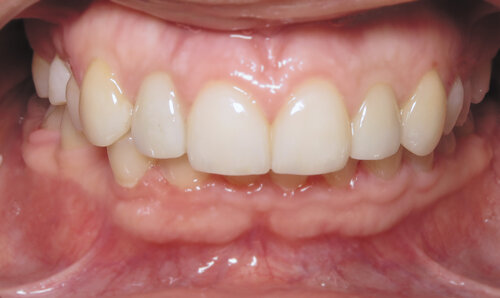

After

We performed a simple gum lift procedure called crown lengthening to improve the shape of the teeth. The result makes them longer and more triangular, which is an aesthetic improvement.